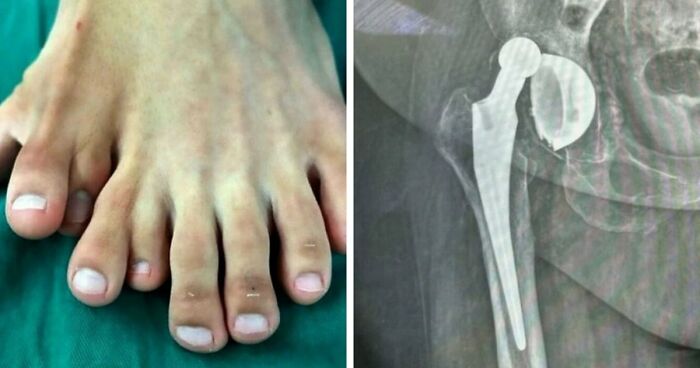

11 If You’re Having A Bad Day, Here Are 79 Painful Photos To Remind You It Can Always Get Worse (New Pics)

If You’re Having A Bad Day, Here Are 79 Painful Photos To Remind You It Can Always Get Worse (New Pics)